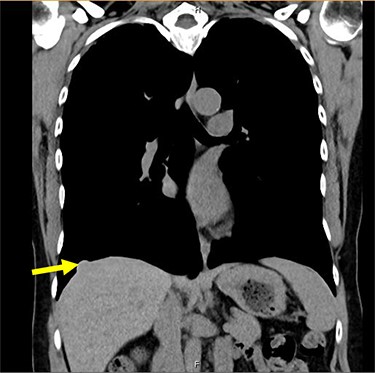

A 54-year-old female without prior thoraco-abdominal trauma presented to the office with two right lower lobe lung nodules. The nodules were initially noted incidentally on a computerized tomography (CT) scan in August 2009 and measured 1.5 cm × 2.8 cm and 0.9 cm × 1.3 cm (Figs 1 and 2). A follow-up CT scan and positron emission tomography (PET) performed in 2010 demonstrated that the nodules were stable in size. The patient was lost to follow-up until March 2019 when she had a CT scan for concern for pneumonia. On these images, the lung nodules had increased in size to 2.8 cm × 4.1 cm and 1.1 cm × 1.4 cm. The patient was otherwise asymptomatic. A PET scan was obtained which showed hypermetabolic nodules with maximum SUV of 3.29 and 1.4, for the larger and smaller nodule, respectively (Figs 3 and 4). Radiographic appearance as well as the growth pattern was consistent with low-grade malignancy suspicious for carcinoid tumor. CT-guided biopsy was not feasible because of location of the tumor.